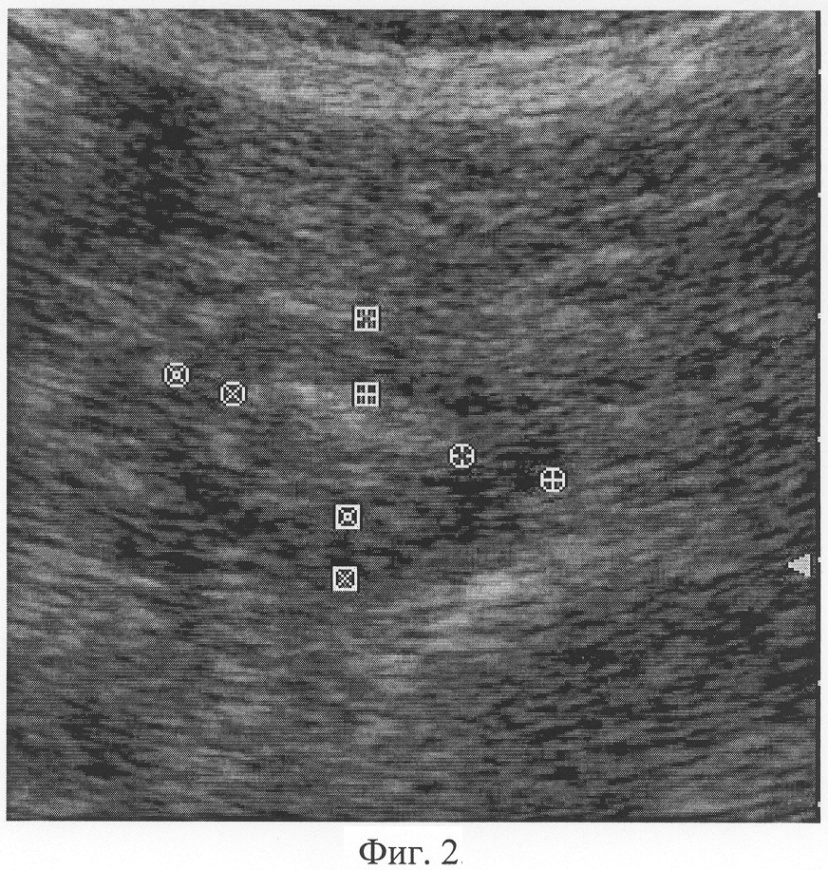

При фиксации изображения в момент полного раскрытия просвета гастродуоденального перехода осуществляют измерение толщины его мышечного слоя, который визуализируется как широкая гипоэхогенная полоска с четкими контурами, расположенная по периферии ультразвукового поперечного среза. Причем измерение толщины производят по передней, верхней, задней и нижней стенкам гастродуоденального перехода, как показано на Фиг.1. Аналогичным образом проводят измерение толщины мышечного слоя гастродуоденального перехода в фазу максимального его смыкания, как показано на Фиг.2.

Фиг.2. Сканограмма (режим серой шкалы, поперечная проекция) гастродуоленального перехода: фаза максимального смыкания, толщина мышечного слоя L1=6,3 мм, L2=7,8 мм, L3=4,9 мм, L4=5,0 мм.